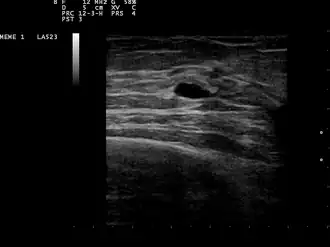

La présence et la nature d'un kyste peuvent être confirmées par une échographie, une biopsie à l’aiguille fine (extraction du contenu par une aiguille)[4] ou une mammographie. L'échographie peut montrer si le kyste contient des nodules solides, un signe qu'il peut être pré-cancéreux voire cancéreux. Un examen de cytologie pathologique des liquides extraits du kyste peut aussi aider au diagnostic, notamment s'il contient du sang.

Une patiente présentant des symptômes d'un kyste passe une mammographie de diagnostic, même s'il n'y a pas de suspicion de cancer du sein. Ce type de mammographie s'accompagne de la possibilité de pratiquer une échographie mammaire. Dans le diagnostic d'un kyste mammaire, l'échographie est privilégiée et considérée comme fiable à 95% voire 100%. Elle fournit une image précise de l'apparence du kyste (simple ou complexe) et peut aussi distinguer une bosse solide d'une poche remplie de liquide, ce pour quoi une simple mammographie n'est pas suffisante[5].